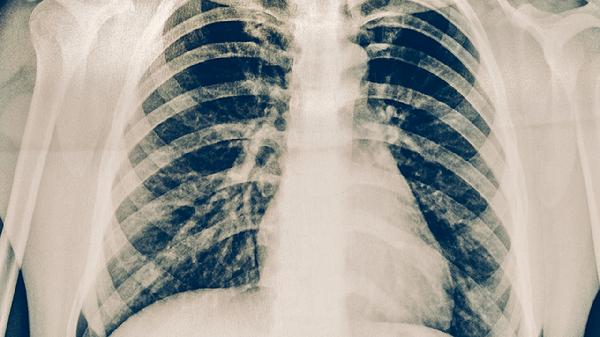

支气管肺炎的严重程度与病原体类型、宿主免疫状态相关。病毒性肺炎常见于儿童,起病较急但多数症状较轻;细菌性肺炎可能出现高热、脓痰,部分患者需住院治疗。支原体肺炎病程较长但较少引发重症。当患者出现持续高热超过3天、呼吸频率增快、血氧饱和度低于93%时,提示病情进展。胸片显示多肺叶浸润或胸腔积液也属于病情加重的表现。